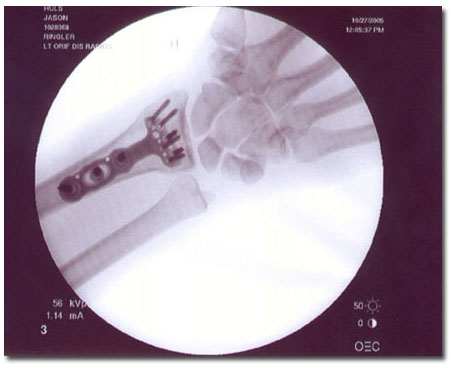

Jason Huls will be that man. Better than he was before. Better. Stronger. Faster.

Bionic Man